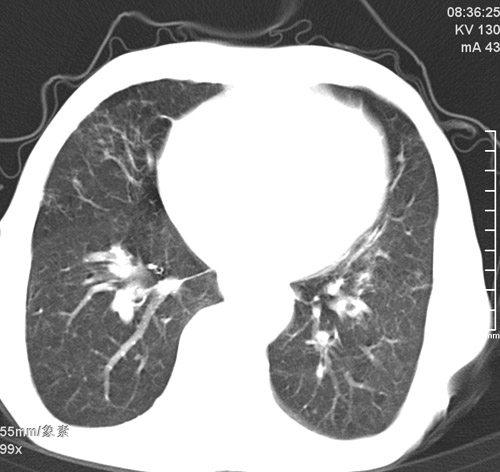

标题: CT17529:男 76 胸背部不适半月 胸透支气管炎 行CT检查 [打印本页]

标题: CT17529:男 76 胸背部不适半月 胸透支气管炎 行CT检查

意见 老年肺 少许炎症 肺大泡 右肺门略大 但支气管通畅  请各位高手指教如何下意见

间质纤维化伴少许炎症!另:肺大泡形成!

支持楼主意见,右肺门略大,可能为肺动脉增粗.

慢支肺气肿,肺动脉高压.